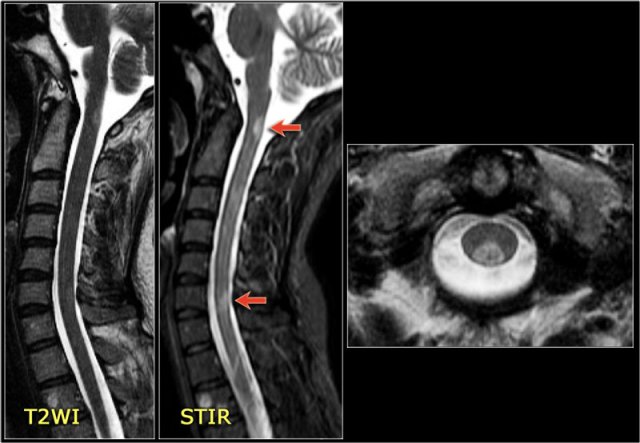

The sagittal image shows a large segment of hyperintensity on T2WI.

The transverse image shows that most of the cord is involved.

These images are of a 31 year old male with headache, voiding disturbances, urinary retention, sensory level C3.

The CSF analysis revealed 400/3 cells (meaning no infection) and a slightly higher protein level.

The images show a long segment myelopathy with full transverse involvement.

There is no swelling and no enhancement.

It does not look like MS or tumor, so we are thinking ATM - acute transverse myelitis.

Here images of a typical case of TM.

There is multisegment high signal on STIR and T2WI with some swelling.

Most of the cord in the transverse diameter is involved.

There is no enhancement, which is usually the case in TM.

Sometimes there is some patchy enhancement.

When there is enhancement, it can be difficult to differentiate TM from an astrocytoma.